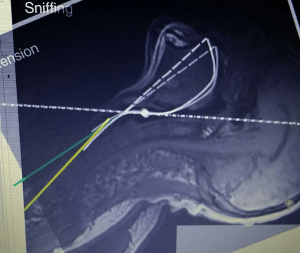

My gut feeling is that it doesn’t work so I rigged up my son to try it out. In my opinion it does not give you head elevation that will allow you to visualize the glottis optimally. With the neck in extension (AO extension) and torso tilted up, the head can still need to be elevated (base of neck flexion moves the head forward on the thorax). Some head elevation may occur because the tilted body shifts down in the bed but it still may not be optimal and you may have a hard time to manipulate the head up and keep it elevated off the end of the stretcher.

If you are ever scoping yourself or someone else, see what a difference doing head forward positioning does to the laryngoscopic view from within the airway (not moving any tissue with a blade to straighten the curves). IMHO it makes your view much better … from grade 2b/3/4 to <=2a. My next nasoendoscopy selfie will have to compare views within the airway of sniffing (Ear to sternal notch) versus extension. See the following video for the AIME demonstration of the effect of head elevation. (PS note that in all of this JAW THRUST is also a crucial piece to straightening the curves and “aligning the axes”).

At the very least, it appears that the tracheal axis is less favorable for tube delivery in the extension position: more tracheal inclination and thus exaggerated corrugation effect from the tracheal rings on tube (tip) delivery.